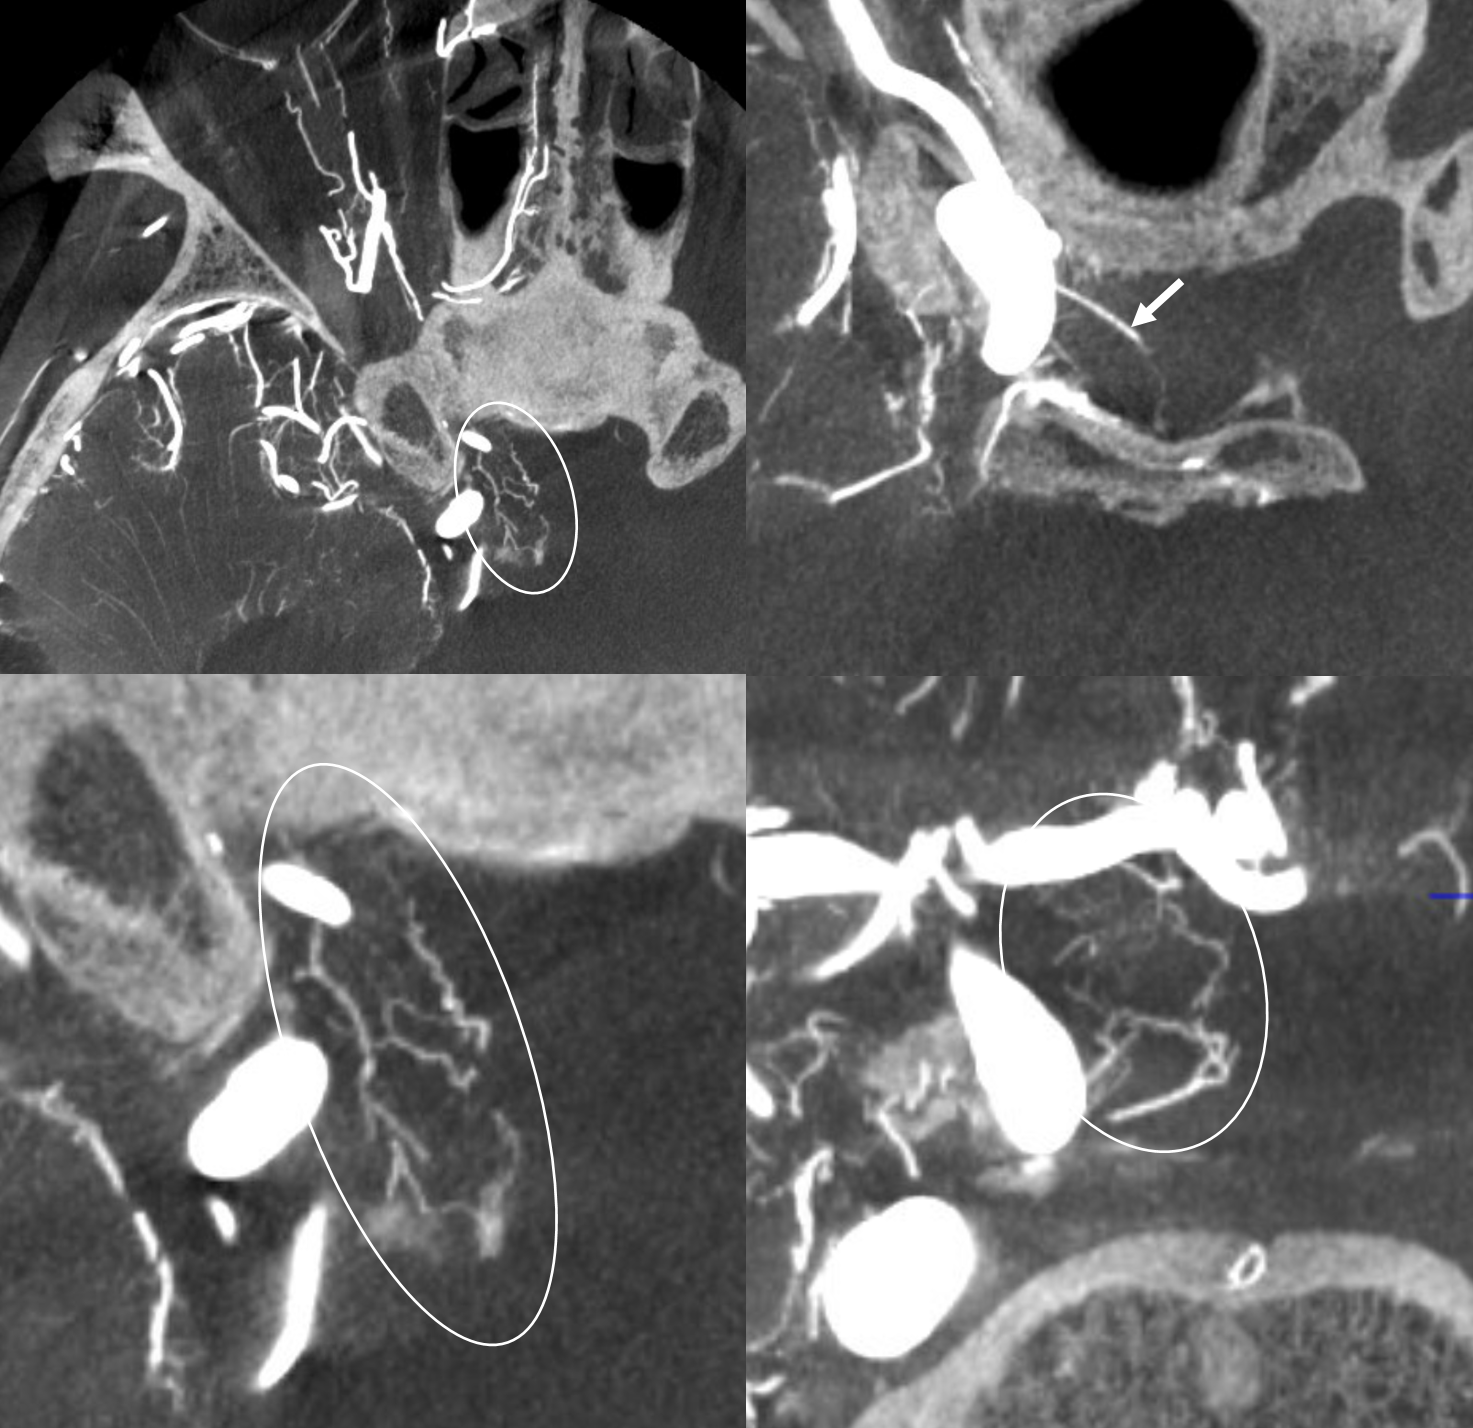

Here there is severe supraclinoid stenosis. Whether because of disease on the other side or other issues, there is extensive takeover of the bilateral optic apparatus by various branches of the left superior hypophyseal arteries. Stereo images shows two main superior hypophyseal artery branches — thats pretty big for the hypophyseals

Bilateral optic apparatus supply (left and right proximal optic nerves, chiasm, proximal left tract) are inside the ovals

Without ovals

Moya-Moya — Similar Process of RIGHT Superior Hypophyseal Reconstitution of the ACA territory, while on left the ophthalmic, via ethmoidal piodural anastomoses, reconstitutes the olfactory branch of the ACA. Full case here

Even more info can be gleaned from MIP images — Whereby on the LEFT, small branches from the proximal ophthalmic — superior hypophyseal equivalents — highlighting the homology between the two — are also present, supporting the optic apparatus and frontal base